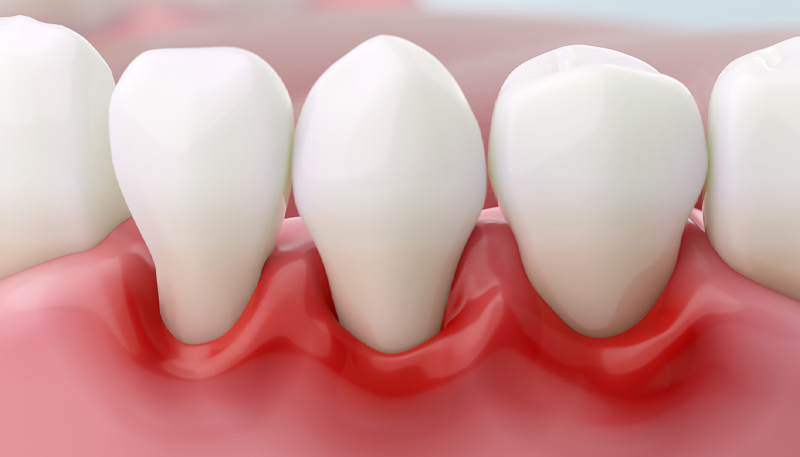

歯周治療

| 顕微鏡による クリーニングSRP |

5,500円 (税込) |

|---|---|

| 再生療法 | 55,000円 (税込) |

| クラウンレングスニング | 16,500円 (税込) |

| フラップオペ | 33,000円 (税込) |